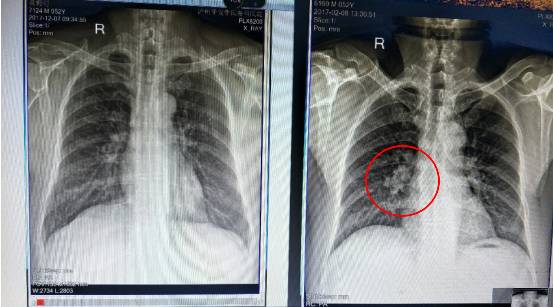

因咳喘,反复感冒等症状来查:

尘肺病阴影,节结ct能查出来吗